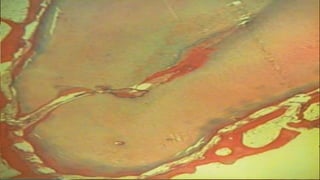

RESORBED APEX

caused due to advanced

inflammation at the

periapex resorption of

cementum and dentin and

widening of apical

foramen

WL determination

,preparation and

condensation of gutta-

percha is difficult-

Preparation should stop

1-2mm short of

radiographic apex